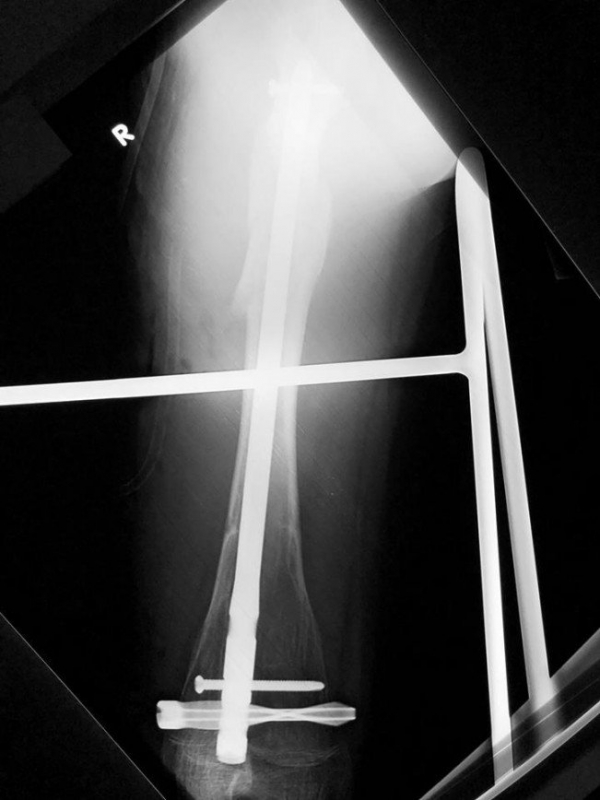

То, что метрополитен – объект повышенной опасности, знают все. Об этом не устают повторять дежурные на станциях, а объявления внутри вагонов знакомят с правилами поведения в любых экстренных ситуациях. Однако предусмотреть всего невозможно.Старшеклассник из столицы попал в Больницу Святого Владимира после поездки на метро. Мальчик упал в подземке, почувствовал сильную боль в ноге и обратился к медикам за помощью. На рентгене стало понятно: у юноши перелом правой бедренной кости. Причем всего год назад он лежал в другой больнице с точно такой же травмой. По всей видимости, кость в бедренной области еще была ослаблена, несмотря на то что в медкарте подростка стояла запись о выздоровлении.

Травматологи Сергей Баранов, Александр Васильев и анестезиолог Елена Дземешко виртуозно провели реостесинтез, сопоставив поврежденные кости с помощью специального блокируемого стержня. Он обеспечивает более эффективное срастание кости и предотвращает осложнения, так как нагрузка при движении распределяется между костью и стержнем.Уже на третьи сутки после операции юноша передвигался на костылях и даже сделал снимок с врачами-спасителями, а сейчас уже восстанавливается дома. Медики предупреждают: будьте внимательны в метро! А если в прошлом у вас были травмы, помните, что они, к сожалению, могут повториться, поэтому будьте предельно осторожны.